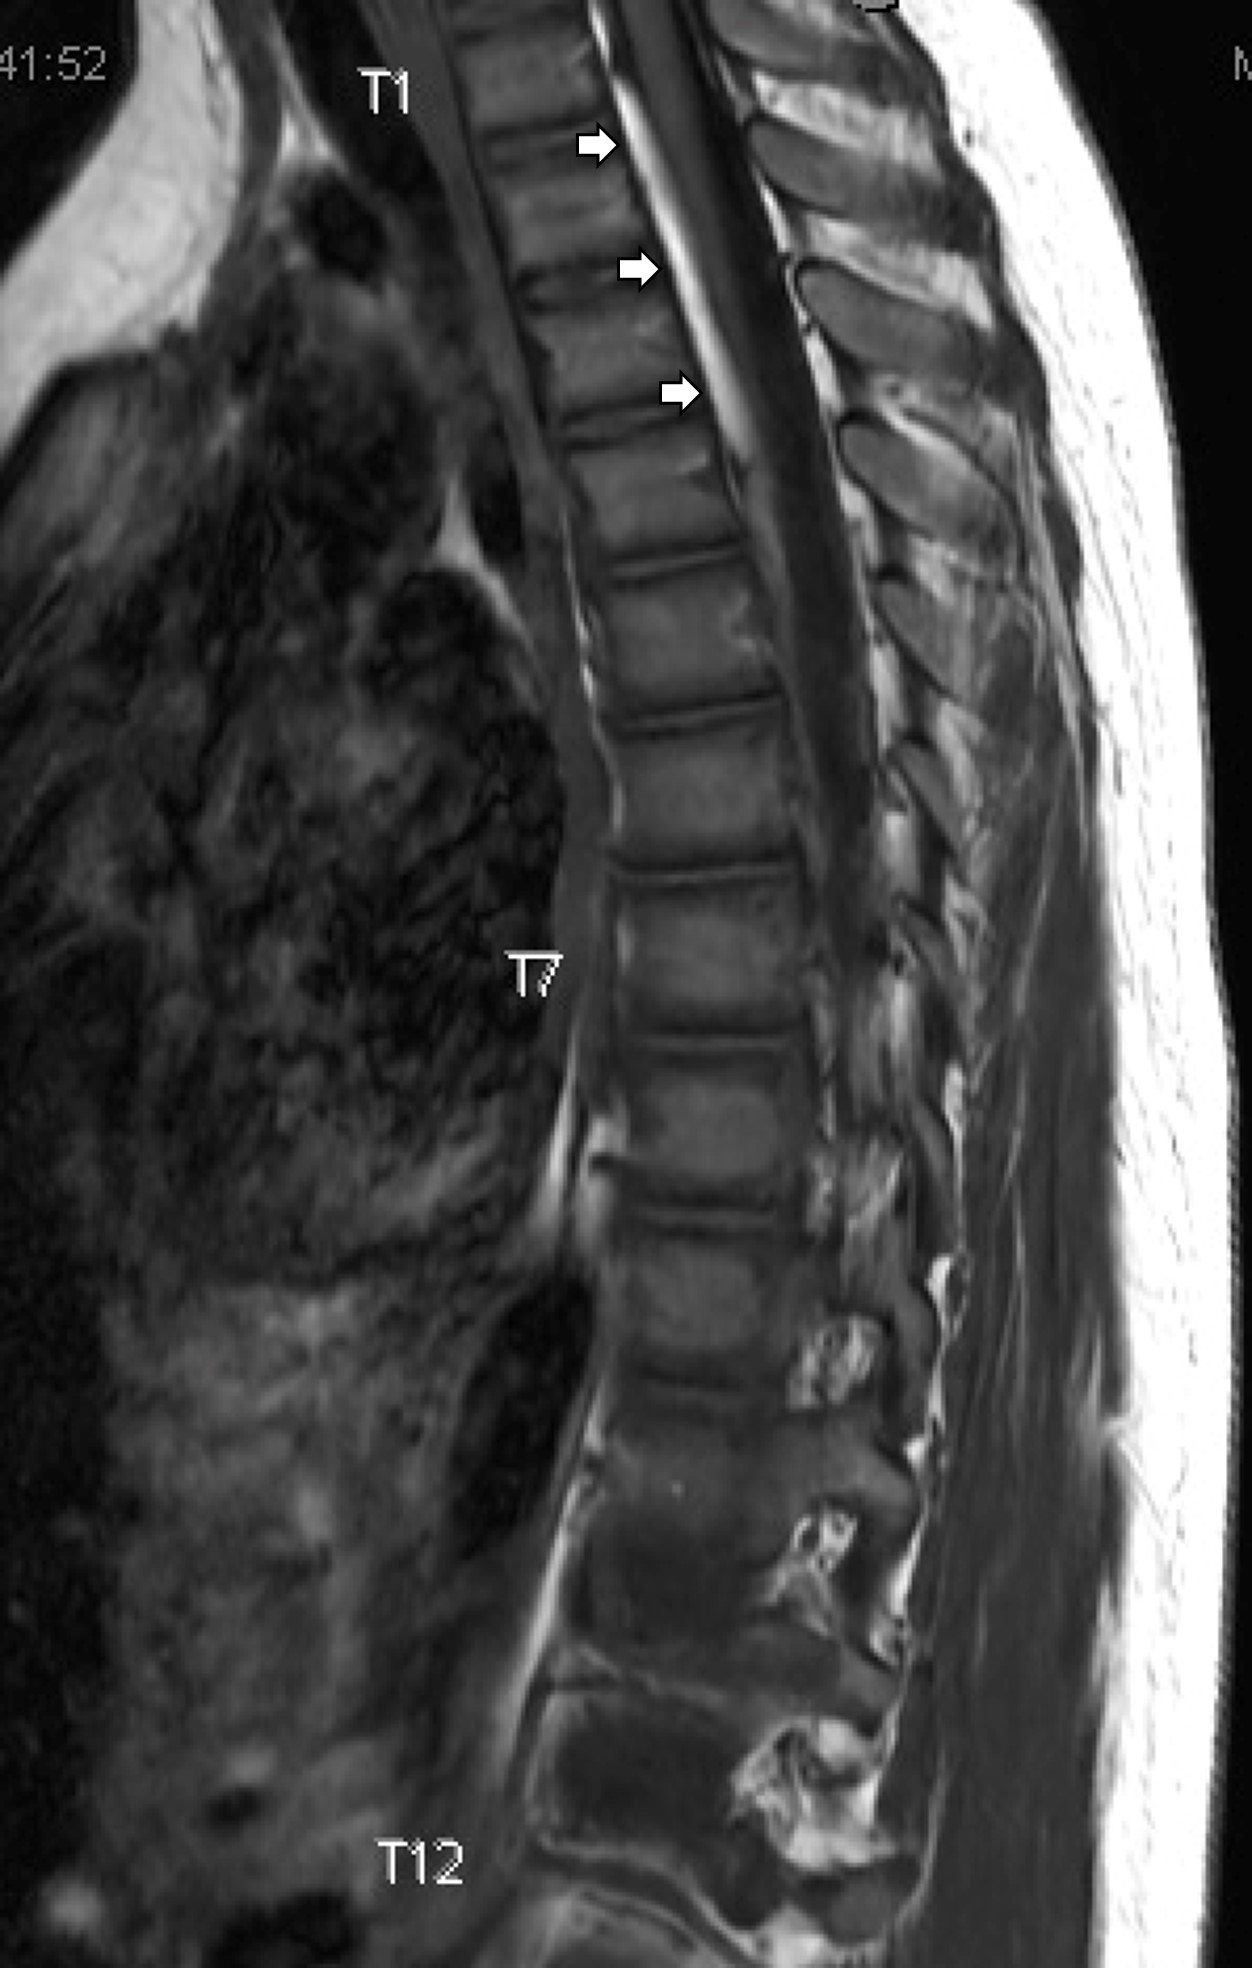

Imaging revealed a cervical subdural hematoma that extended into the thoracic region. Subsequent MRI images of the thorax and lumbar spine were obtained. The patient was admitted for observation, pain control, and neurosurgery evaluation. There was no surgical intervention, and the patient was cleared by physical therapy and occupational therapy for home, and the patient will follow up with neurosurgery for repeat MRI images.

Spinal subdural hematomas (SDH) are rare conditions.1,2 Causes of SDH include percutaneous spinal interventions (eg, lumbar punctures, acupuncture3), back surgery, hematologic disorders, anticoagulation use, and/or trauma. Trauma is an uncommon cause of spinal SDH.1

The exact mechanism of SDH amongst trauma patients is unclear. As the subdural space is relatively avascular, it has been postulated that spinal SDHs are the result of downward migration of blood from intracranial SDH.2,3,4 However, it is unclear if these are separate incidences that occur concomitantly.5 In a subset of pediatric patients, spinal SDH can be seen in children with abuse head trauma.6 Clinicians should be aware of this potential injury in trauma patients.